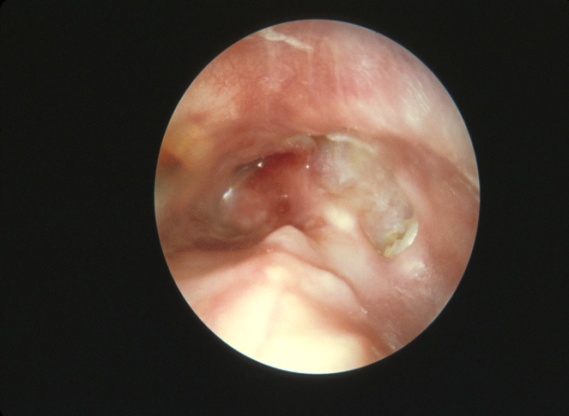

成形的膽脂瘤須進行乳突手術治療(mastoidectomy)。手術目標是割除膽脂瘤,除去被膽脂瘤破壞的耳膜和耳骨,將乳突打開,修補耳膜和耳骨,擴闊耳道入口(meatoplasty)。修補耳膜最常用耳上方的顳肌膜(temporalis muscle fascia),修補耳骨則可用人造耳骨或將損壞的耳骨重新排列。術後需定期以顯微鏡輔助,吸出傷口分泌物,耳內傷口需2個月時間才完全康復,康復後可見如圖三所示乳突和耳道合併空腔,以及成功修補的耳膜。

■圖三